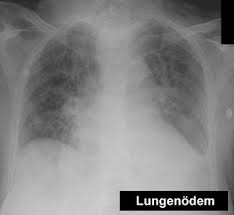

Wasser in dr lunge. Allerdings sei der linke Lungenflügel beeinträchtigt aus irgendeinem Grund könne er sich nicht richtig entfalten. 2021 Google LLC. Wasser in der Lunge oder im Lungenspalt behindert die Atmung und den Sauerstoffaustausch.

Ursachen von einem Lungenödem Einer der häufigsten Ursachen für Wasser in der Lunge ist eine Herzschwäche Herzinsuffizienz. Das Wasser in der Lunge entsteht dadurch dass Blutflüssigkeit aus den Blutgefäßen austritt und sich im umliegenden Lungengewebe und den Lungenbläschen ansammelt. Fortschreitendes und akutes Lungenödem Wenn die Flüssigkeit in die luftgefüllten Hohlräume der Lunge eindringt dann handelt es sich um ein alveoläres Lungenödem.

Mögliche Folgen sind Atemprobleme bis hin zum Atemstillstand. Anfangs sammelt sich das Wasser im Stützgewebe der Lunge interstitielles Lungenödem. Dictcc Übersetzungen für Wasser in der Lunge im Latein-Deutsch-Wörterbuch mit echten Sprachaufnahmen Illustrationen Beugungsformen.

Das Lungenödem auch Wasserlunge und pulmonales Ödem genannt beschreibt eine Flüssigkeitsansammlung in der Lunge. Blutrückstau und Wassereinlagerungen in Ihrer Lunge erschweren die Atmung und lösen Hustenreiz aus. Zunächst wird sich Wasser in dem Lungenzwischengewebe ansammeln welches dann im fortschreitenden Status die Lungenbläschen angreift.